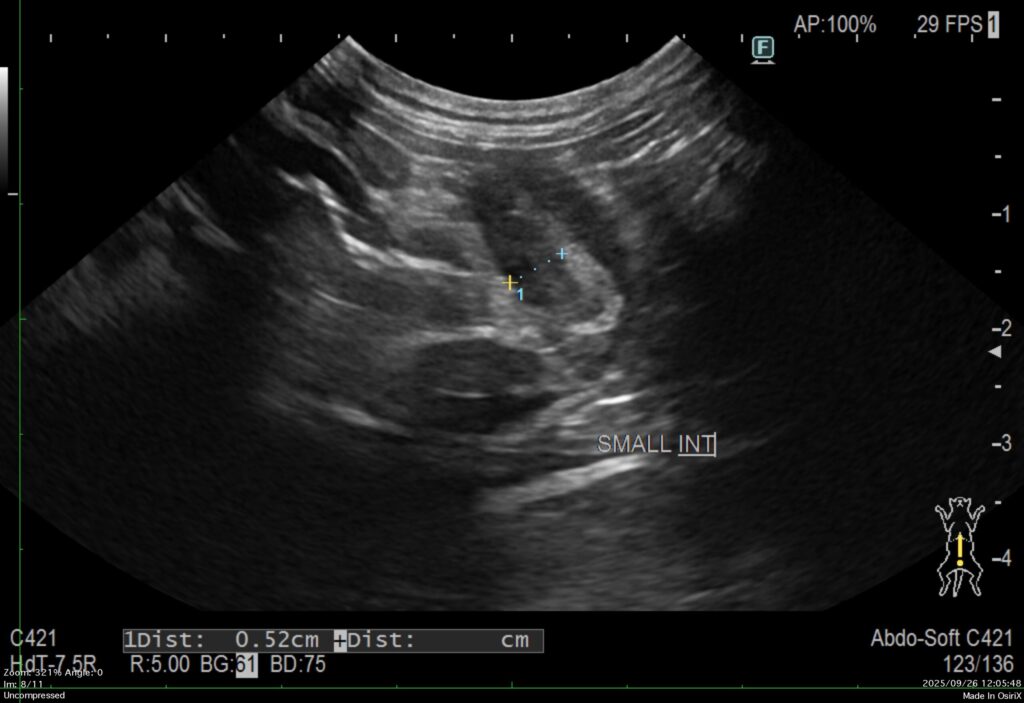

犬のリンパ腫全体の5~7%に認められるタイプです。腸間膜リンパ節や腸管が腫れるため、下痢、嘔吐、体重減少、食欲不振などが生じます。超音波検査や内視鏡検査を行うことで発見することができます。

診断は、犬のリンパ腫と同様です。触診、血液検査、レントゲン検査、超音波検査により全身のリンパ組織の状態を把握します。胸部レントゲン検査により縦隔の腫瘤や胸水の有無を確認します(縦隔型)。腹部レントゲンにより腹部臓器の大きさや位置を確認します(消化器型、多中心型、腎臓型)。超音波検査は、腹部臓器を詳細に検査できます。